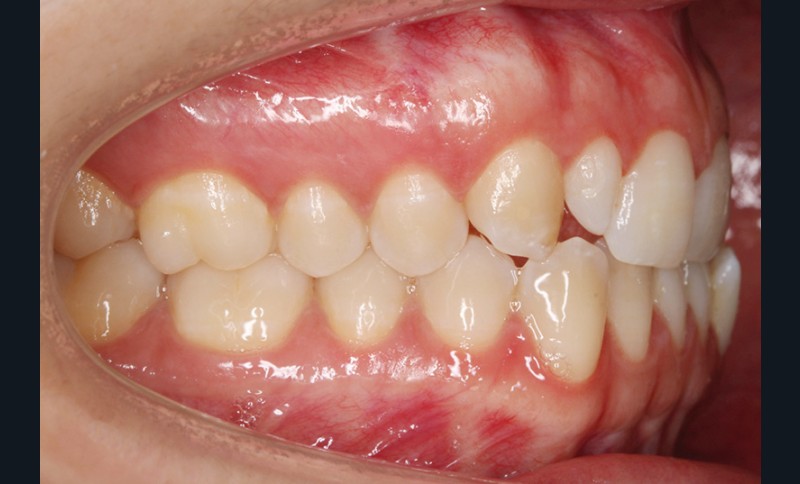

Elle présente une classe I dentaire en denture adulte. Son sourire est perturbé, notamment par la microdontie de son incisive latérale maxillaire droite (la 12). On constate un encombrement modéré au maxillaire (bimarginotopie mésio-palatine et disto-vestibulaire de 13) et plus marqué à la mandibule (monomarginotopie mésio-vestibulaire de 32 et de 43) (fig. 1-6).

Les milieux inter-incisifs ne sont pas coordonnés, à torts partagés, avec une légère déviation à droite du milieu inter-incisif maxillaire et une déviation plus marquée à gauche du milieu inter-incisif mandibulaire ainsi que du point menton. 32 et 33 présentent une tendance à l’exoclusion.